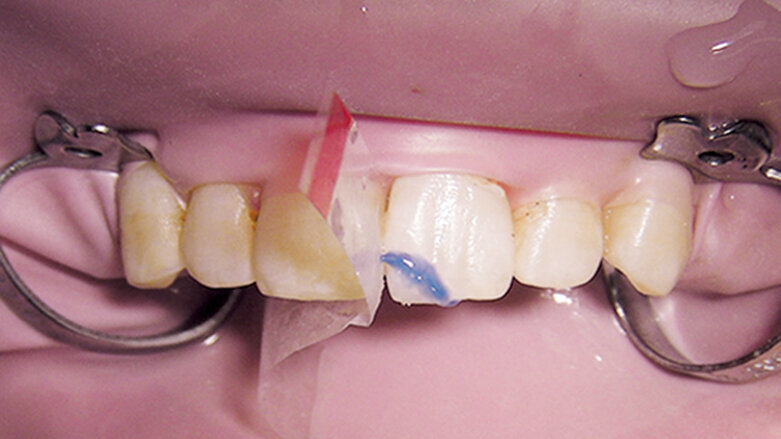

Obr. 1a: Klinický případ dvou nekomplikovaných fraktur korunky, kdy dva ulomené fragmenty byly nalezeny a znovu připevněny (fotografie poskytnuty American Association of Endodontists)

Fraktury korunky

První, co je třeba udělat u jakékoliv korunkové nebo korunko-kořenové fraktury, je pokusit se najít odlomený fragment zubu. S moderní bondovací technologií je možné znovu spojit odlomený fragment se zbytkem zubu, což je esteticky nejlepší řešení. Ještě před připojením fragmentu zubu musí být tloušťka vrstvy zubu mezi pulpou a povrchem zhodnocena radiologicky a klinicky. Pokud zbývá alespoň 0,5 mm dentinu, není nutno místo překrývat ochrannou podložkou. Pokud je stanoveno, že zbytkový dentin je méně než 0,5 mm široký, je doporučeno překrýt oblast fraktury nejblíže u pulpy podložkou a tvarově přizpůsobit spojovací plochu fragmentu. Pokud byl fragment zubu držen v suchu, měl by být rehydratován v destilované vodě nebo slině po dobu 30 minut před spojováním, což zvýší vazebnou sílu (obr. 1a–c).